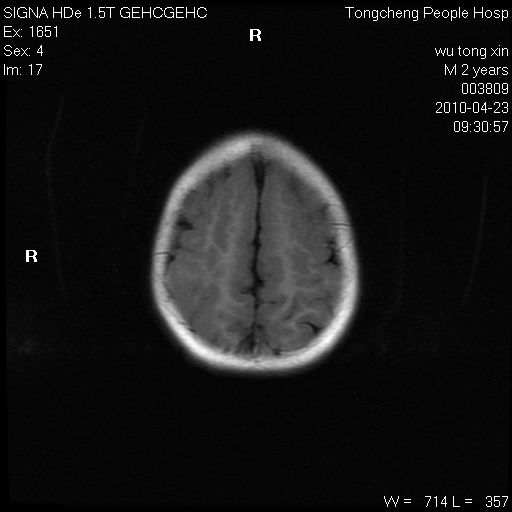

以下是引用赵物学在2010-4-25 12:43:00的发言:[br]巨脑回[br]侧脑室后角低密度影考虑hie或肾上腺脑白质营养不良?[br][br][本贴已被 赵物学 于 2010-4-25 12:51:28 修改过]

以下是引用gaoxiao在2010-4-25 16:54:00的发言:[br]巨脑回畸形。脑白质髓鞘化不良

以下是引用pujunzhi在2010-4-25 21:35:00的发言:[br]考虑 1双侧大脑皮质发育不良 2轻度脑积水 3双侧脑室后角旁片状长t1长t2信号,需继续观察,因为正常小儿此处脑白质的髓鞘化时间可以延迟到4-6岁,才显示正常。